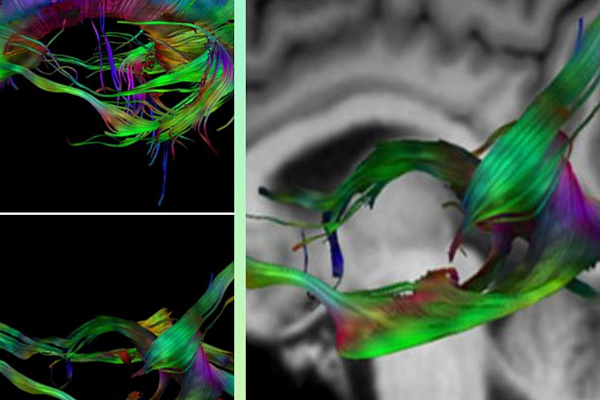

Рентгенологи постоянно изучают новые методы и технологии исследований, обеспечивая дальнейшее безопасное и эффективное лечение пациентов. Например, используя диффузно-тензорную томографию (трактографию) головного мозга, диагносты помогают нейрохирургам проложить маршрут операции так, чтобы не повредить важные пути и центры. Освоили наши специалисты и один из самых молодых методов лучевого исследования головного мозга - магнитно-резонансную спектроскопию, позволяющую определять химический состав опухолей и других патологических зон.